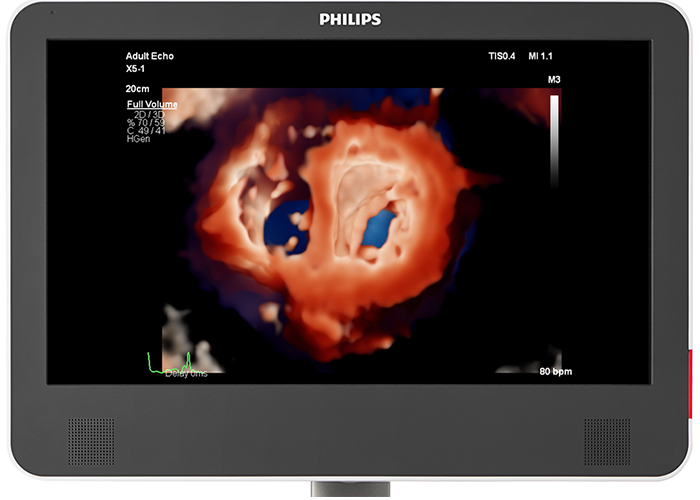

Photorealistic rendering built for collaborative intervention suites For better visualisation of interventional devices, Philips cardiology TrueVue, with its virtual light source, is a proprietary and advanced 3D ultrasound display method. TrueVue makes it simpler to visualise the location of catheters and devices by providing images with tissue detail and depth perception. Since it offers a viewing context for the echo images, caregivers in the interventional suite can rely on support when communicating complicated echo images and enhance their procedural confidence. 90% of clinicians5 who saw the new Philips EPIQ CVx felt the new TrueVue 3D photorealistic rendering improved viewing of anatomical structures thus increasing clinical confidence2.

Photorealistic rendering built for collaborative intervention suites

For better visualisation of interventional devices, Philips Cardiac TrueVue, with its virtual light source, is a proprietary and advanced 3D ultrasound display method. TrueVue makes it simpler to visualise the location of catheters and devices by providing images with tissue detail and depth perception. 90% of clinicians5 who saw the Philips EPIQ CVx felt the new TrueVue 3D photorealistic rendering improved viewing of anatomical structures thus increasing clinical confidence2 .